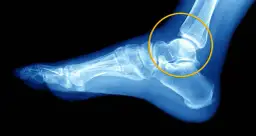

Czy RTG jest zawsze konieczne? Rola prześwietlenia w wykluczaniu złamań

Tak, zdjęcie rentgenowskie (RTG) jest niemal zawsze konieczne po urazie stawu skokowego, zwłaszcza jeśli występują objawy alarmowe lub trudności w obciążaniu nogi. Jego głównym celem jest wykluczenie złamania kości. Skręcenie i złamanie mogą dawać podobne objawy, dlatego precyzyjna diagnostyka jest niezbędna, aby dobrać odpowiednie leczenie. Wykluczenie złamania daje pewność, że możemy skupić się na leczeniu tkanek miękkich.USG stawu skokowego: Co pokaże badanie i dlaczego jest tak ważne?

Po wykluczeniu złamania często wykonuje się badanie ultrasonograficzne (USG) stawu skokowego. USG jest niezwykle ważne, ponieważ pozwala ocenić stan tkanek miękkich przede wszystkim więzadeł, które są najczęściej uszkadzane podczas skręcenia. Dzięki USG lekarz może określić stopień uszkodzenia więzadeł (naciągnięcie, częściowe zerwanie, całkowite zerwanie), obecność płynu w stawie czy krwiaków. Ta informacja jest kluczowa dla zaplanowania dalszego leczenia i rehabilitacji.